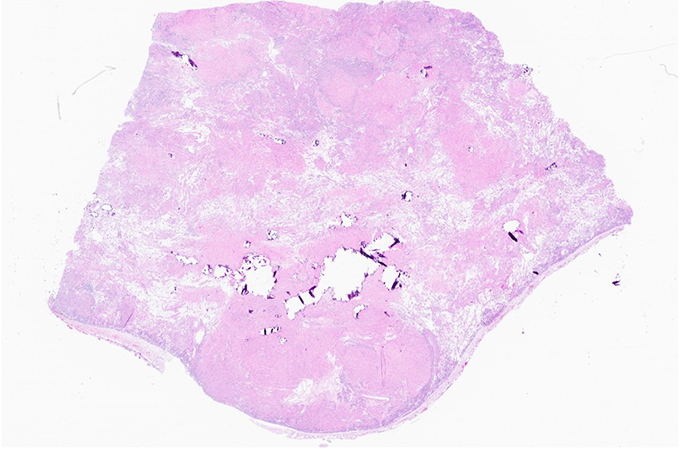

An excision was performed and histology shows a well-circumscribed spindled and focally epithelioid neoplasm arranged in fascicles and nests. At low power, the tumor has a vaguely nodular appearance (Figure 1). There are areas with increased cellularity alternating with areas with relatively less cellularity, some of which have a prominent hyalinized stroma, while others have a somewhat edematous appearance (Figures 2, 3). The cells have eosinophilic cytoplasm and ovoid nuclei with finely-stippled chromatin and small nucleoli. The cytomorphology is predominantly bland. Rare mitoses are identified (1 per 2 mm2) but necrosis is not conspicuous (Figure 4). There are occasional ectatic vessels as well as coarse calcifications of varying sizes scattered throughout, including small psammoma bodies (Figures 5, 6).